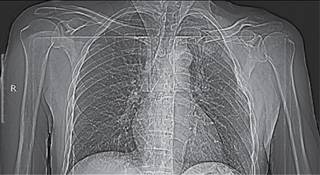

Masculino de 50 años de edad que al trasladarse en bicicleta sufrió traumatismo directo al caer de tres metros de altura sobre hombro izquierdo, manifestando de inmediato dolor intenso en cintura escapular izquierda, deformidad de la región e imposibilidad de movimiento por dolor de la extremidad ipsilateral. Relata que acudió con empírico quien le “acomodó” y aplicó vendaje tipo Velpeau “muy apretado”, dos semanas después de la lesión acude a urgencias por presentar fiebre y supuración en región esternoclavicular izquierda. A la exploración: temperatura de 38 oC; TA 120/80; FC 100X’; FR 18X’, se observan múltiples tatuajes, se retira vendaje serosanguinolento de olor fétido, encontrando zona de 2 cm de diámetro de pérdida de sustancia que permite ver hueso sobre área de articulación esternoclavicular izquierda (Figura 1) a además de deformación de cintura escapular izquierda, el resto de la exploración de tórax y abdomen normal. El examen clínico muscular mostró: trapecio izquierdo y deltoides con calificación 3/5 por dolor, resto de músculos examinados en extremidad superior izquierda en 4/5 por desuso al compararlos con la extremidad contralateral, sensibilidad conservada, reflejos osteotendinosos normales al igual que pulsos arteriales y llenado capilar digital. Se tomó cultivo de zona de lesión en el momento de la debridación, se solicitó laboratorio, tomografía computarizada de tórax (Figuras 2 y 3) electrocardiograma y se le hospitalizó. Se inició tratamiento antibiótico empírico con ceftriaxona 1g una vez al día y clindamicina 600 mg dos veces al día. El electrocardiograma y la telerradiografía de tórax con silueta cardiaca y campos pulmonares revelaron fractura luxación bipolar de clavícula izquierda, la tomografía con reconstrucción helicoidal confirmó sus características. La lesión proximal de clavícula se catalogó en AO 15.B de tipo III B según la clasificación de Gustillo-Andersen y la lesión distal de clavícula en AO 15.3A1. Al cabo de 48 horas el cultivo reportó Staphylococcus epidermidis. Se decidió después de 10 días de antibioticoterapia y con resultados de segundo cultivo negativo efectuar ostectomía de 1.4 cm de la porción medial de clavícula, reconstrucción del ligamento costoclavicular y cierre de área con colgajo con inmovilización mediante cabestrillo reforzado con cinturón en velcro por cuatro semanas. En el seguimiento entre 10 y 20 días el paciente mostró buena evolución sin dato de infección, a las cuatro semanas se retiraron puntos y se canalizó a rehabilitación, a los 60 días del programa de rehabilitación el paciente fue dado de alta con calificación 15/100 en la escala de DASH (Disability of the Arm Shoulder and Hand), con arcos de movilidad limitados en los últimos 10o para la rotación interna y 15o en abducción de hombro, sin dolor.

Figura 2: Pantograma de tórax (tomografía computarizada) que muestra luxación de articulación acromioclavicular izquierda y fractura distal de clavícula (AO 15.3A1), así como luxación esternoclavicular y fractura proximal de la clavícula izquierda (AO 15.B ).